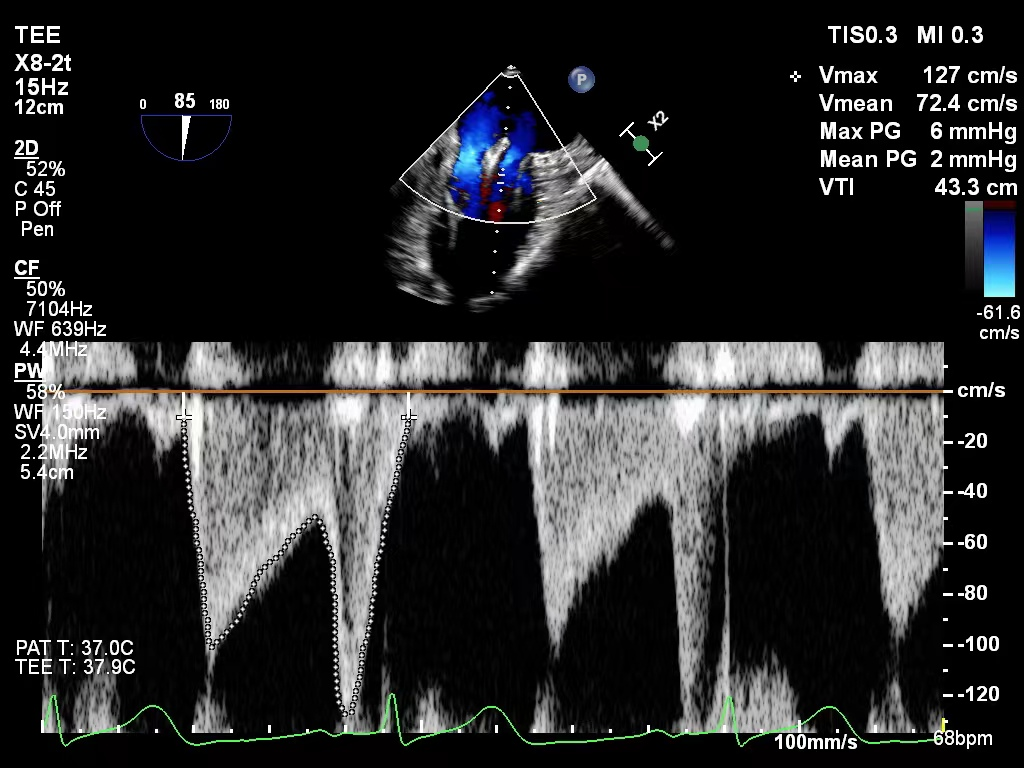

二尖瓣口平均跨瓣压差:2mmHg

图片

肺静脉血流频谱恢复正向